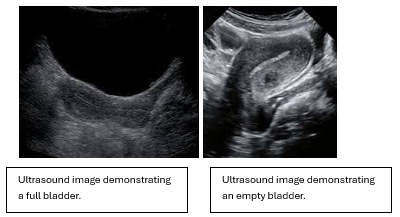

So many “workarounds” it seems regarding the full bladder, and yet, the full bladder is an important part of a transabdominal scan. The full bladder gives a structural landmark that helps orient the imager to the pelvic area. The full bladder pushes the bowel away from the area, allowing for better resolution. A full bladder will also provide what is referred to as a “sonic window”. The sound wave travels through the fluid-filled bladder unimpeded so that when it reaches the uterus, it has a greater intensity than the portion of the sound beam that has traveled through the adjacent soft tissue. This allows for better resolution. Ideally, the bladder should always extend past the fundus of the uterus. Always. The quality of images obtained with a full bladder as opposed to a partially full or completely empty bladder is worth the wait. A full bladder gives the imager a reference for the level of gain necessary for the exam. (This is true as long as the bladder is normal and anechoic)

A possible soft tissue area adjacent to the uterus may appear as a mass without a full bladder. By filling the bladder, if the area is simply bowel, it may move or entirely disappear. The anteverted or anteflexed uterus will be stretched out lengthwise with a full bladder. With an empty bladder, it will remain in one area, making it difficult to thoroughly image the uterus. Sometimes images can be obtained with an empty or partially filled bladder, but too often the payoff of questionable quality images or remaining questions isn’t worth the time that was saved by not filling her bladder. The first question to be asked when evaluating a scan of the uterus will be why the bladder isn’t full. It is standard practice transabdominally.